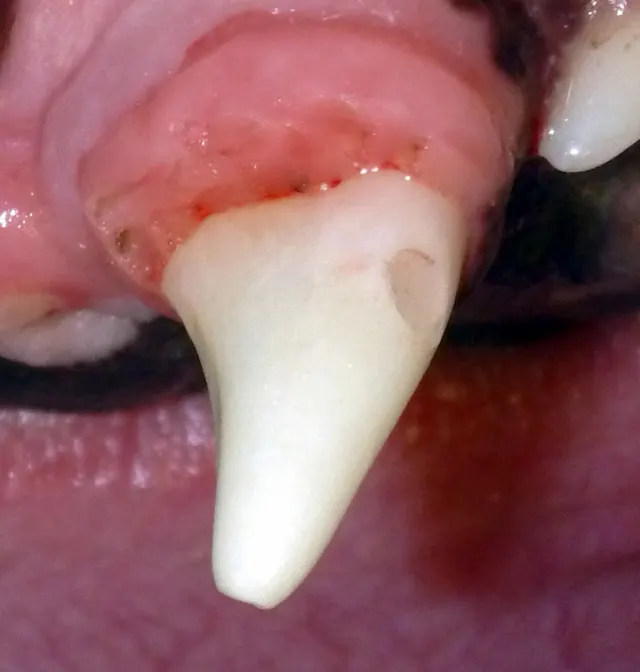

Resorbing deciduous (primary) left mandibular fourth premolar.

In rare forms of tooth resorption, the root’s dental hard tissue is replaced by bone. The root will appear to have less radiopacity when compared with adjacent normal roots. The remaining crown’s height can be reduced to a subgingival level via amputation and sutured closed.